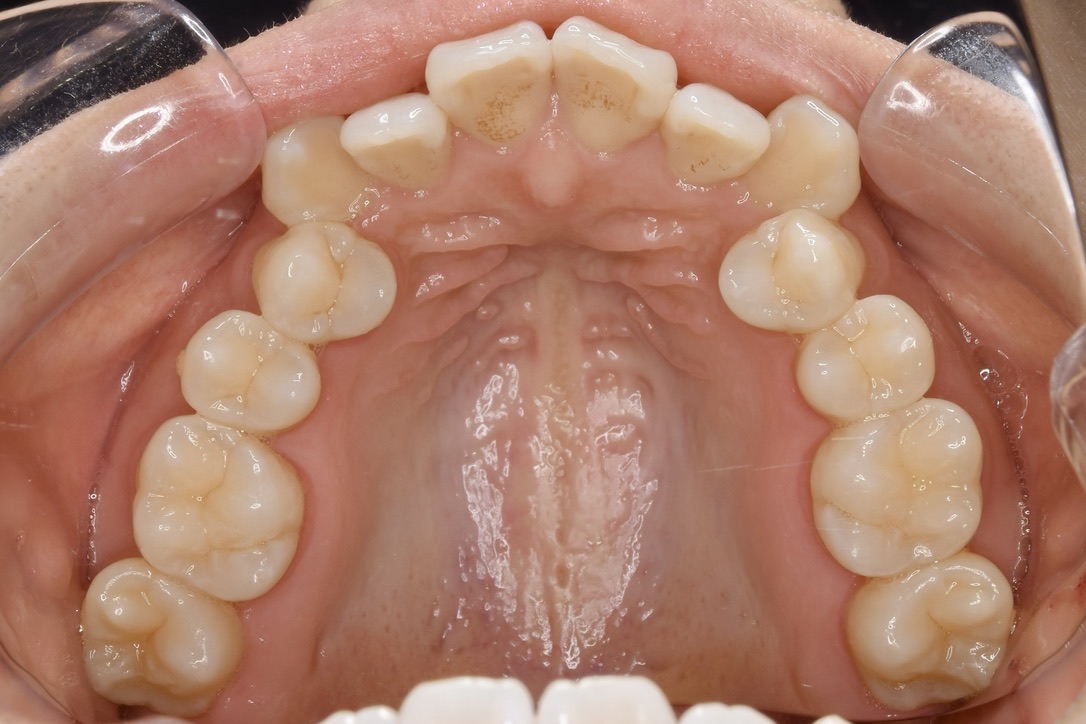

| 主訴 | 写真を見て歯並びが気になる。特に下の前歯はガタガタが強く治したい。 |

|---|---|

| 診断名・主な症状 | 叢生 |

| 年齢 | 19歳 |

| 治療内容 | 上下とも歯並びの幅を広げることでできたスペースを利用して、ガタガタを解消しました。 |

| 使用装置 | 表側矯正(ワイヤー) 矯正用ミニインプラント |

| 抜歯部位 | 抜歯なし |

| 治療期間 | 1年10ヶ月 |

| 通院回数 | 25回 |

| 費用 | 91万円程度(税別) 220 |

| リスク・副作用 | 痛み、歯肉退縮、歯根吸収、抜歯に伴う出血や腫れが生じることがあります。 |